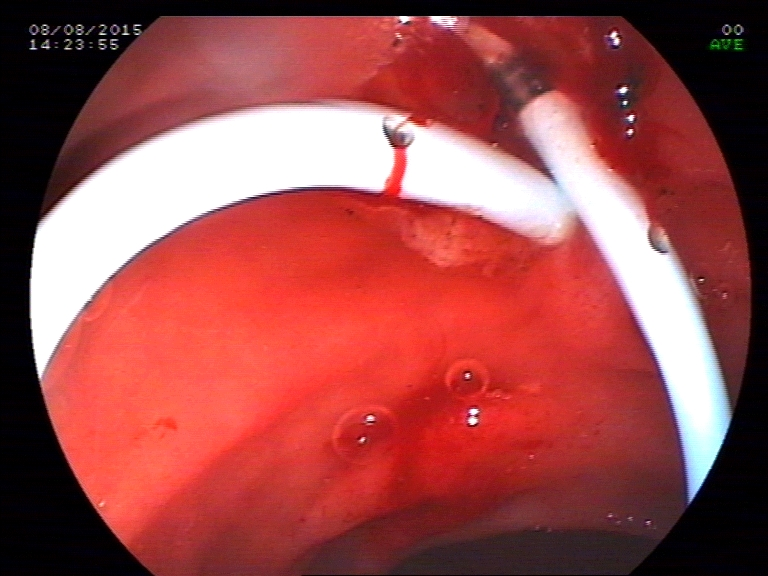

ERCP was done to remove the stone from the bile duct.Patient was sent bacl for laproscopic cholecystectomy and advised to come for removal for stent removal, a month later.